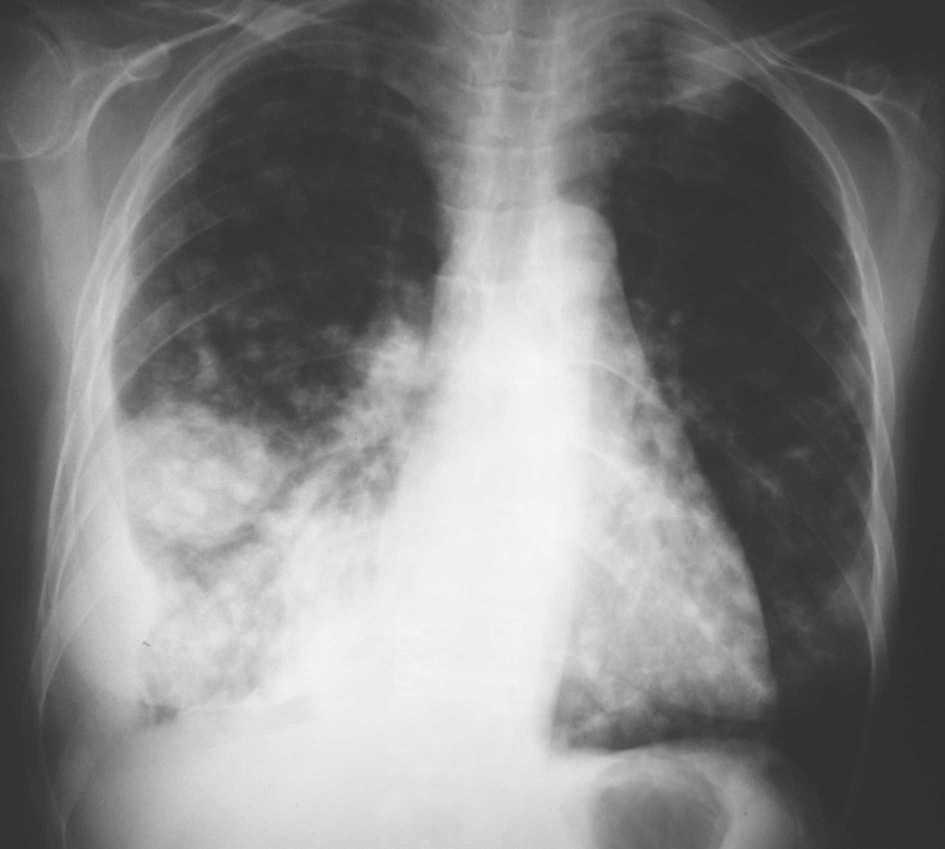

Fig. 1. Radiografía posteroanterior de tórax.

Mujer de 34 años de edad, con antecedentes de lupus eritematoso de complicado control que obliga a un tratamiento prolongado con dosis altas de corticoides. Presenta clínica de un mes de evolución de astenia, tos y febrícula con sudoración profusa en los últimos 10 días, que evoluciona con deterioro progresivo y disnea de reposo.